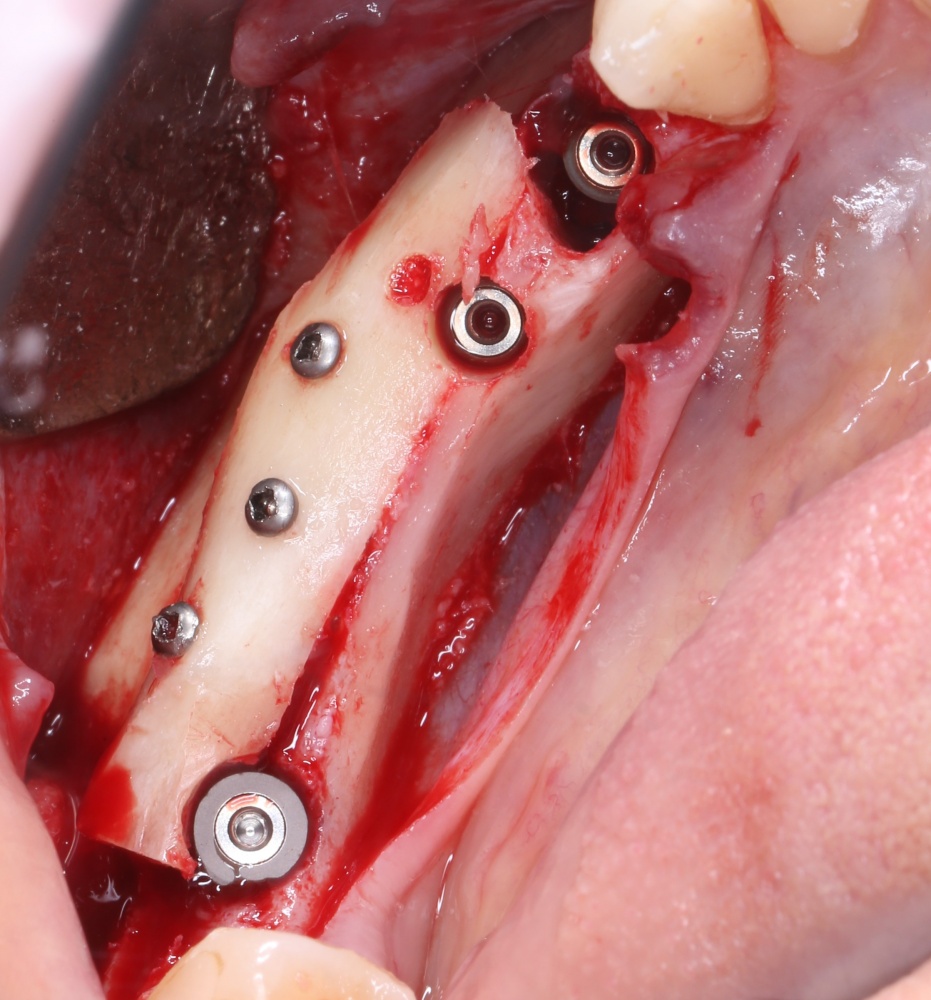

Вернемся к нашему клиническому случаю. Мы уже поставили импланты с расчетом на будущую высоту альвеолярного гребня и положение будущих зубов:

И, если в предыдущей части мы рассматривали ситуацию, когда принимающее ложе имеет относительно простой рельеф, и у нас не возникло сложностей с адаптацией аутоблока, то в случае, рассматриваемом сегодня, нормальная и точная адаптация крупного костного фрагмента, практически, невозможна. Именно поэтому мы решили использовать направленную костную регенерацию (НКР), поскольку с адаптацией тестообразного по консистенции графта проблем, обычно, никогда не бывает. Как, например, в этом случае:

В описываемом клиническом случае нам нужно замещать достаточно большой объем костной ткани, поэтому использование ксенографта (Geistlich Bio-Oss) выглядит совершенно разумным. Мы смешиваем его с аутокостной стружкой, источником клеток и факторов роста костной ткани, в пропорции, примерно 50/50, получая, при этом, около 3 куб см готового к использованию графта:

С помощью него мы «достраиваем» недостающую часть альвеолярного гребня, полностью перекрывая импланты. Напомню, что субкрестальные Ankylos Dentsply Implants вполне допускают такой подход.

Костная ткань, в отличие от слизистой оболочки, регенерирует очень медленно. Если ее не отделить от быстрорастущих тканей, то место, где должна регенерировать костная ткань, быстро заполняется грануляциями — и, в итоге, для кости не остается пространства для роста. Чтобы отделить одно от другого, используются коллагеновые барьерные мембраны.

В нашем случае мы используем Geistlich Bio-Gide. Почему? Потому, что, имхо, это лучшее, что есть на рынке барьерных мембран. Почему? См. RegenerationDay.